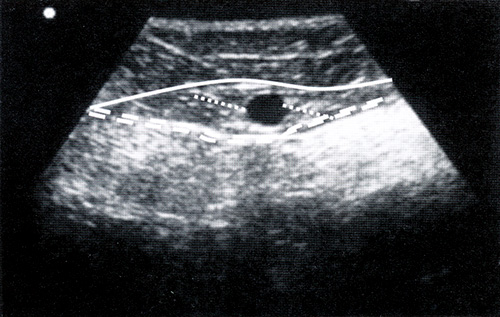

Ультразвуковая анатомия вен подразделяет их на вены трех уровней: глубокий (под глубокой фасцией), промежуточный (между глубокой и поверхностной фасцией), подкожный (над поверхностной фасцией). Во время исследования врач определяет местоположение вены, ориентируясь на окружающие анатомические структуры – кости, фасциальные пластинки, мышцы, глубокие сосуды. А также существует ряд ультразвуковых признаков, используемых для идентификации вен.

Симптом «глаза» используется для определения вен, располагающихся в расщеплении поверхностной фасции: БПВ, МП, вены Джакомини, латеральной передней подкожной вены.

Диагностика варикоза

Симптом «строя». Большая подкожная вена и ее передний приток (передняя добавочная подкожная вена, ПДПВ) на поперечном срезе, сделанном на уровне верхней трети бедра, часто дают два симптома «глаза». В то же время ПДПВ лежит спереди и латерально по отношению к БПВ. При УЗДГ ее расположение меняется:она находится на одной линии над бедренной артерией и веной.

При УЗДГ в случае аплазии БПВ за симптом «глаза» «отвечает» ПДПВ, о чем можно судить по тому, что он (симптом) располагается над бедренной артерией и веной.